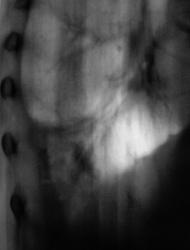

Сегодня произвели "очередной контроль". Произвели рентгенографию в прямой и правой боковой проекциях. Решили также произвести томографию в правой боковой проекции.

Катенёву В.Л.: На боковых томограммах, впечатление о инфильтрации с распадом в S10; томограммы, вероятно выполнены в положении лёжа, следовательо следует ожидать, что выпот растекся по грудной стенке и  не виден. С учётом характера распада, не исключаеиться туберкулёзный процесс.

О "выпоте" думали даже сначала, но только об осумкованном. Сегодня при дообследовании, "полостное образование" было неожиданной находкой, но о "туберкулёзной" этиологии, именно полостного образования, не думали. Но интересно, что пациент себя (с его слов) чувствует себя хорошо. ПО ВСЕЙ ВИДИМОСТИ, ОТПРАВИМ В ОБЛАСТЬ К ПУЛЬМОНОЛОГАМ.